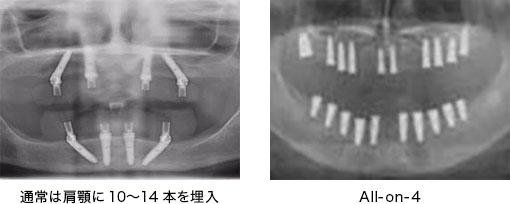

通常のインプラント治療では

歯が1本もない場合、インプラントを10本〜14本埋め込むことが一般的です。

All-on-4 (6)では少ない本数で入れ歯を支えます。